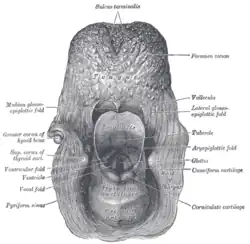

Vue laryngoscopique de l'orifice glottique.

Vue laryngoscopique de l'orifice glottique.

Entrée du larynx, vue postérieure.

Entrée du larynx, vue postérieure.